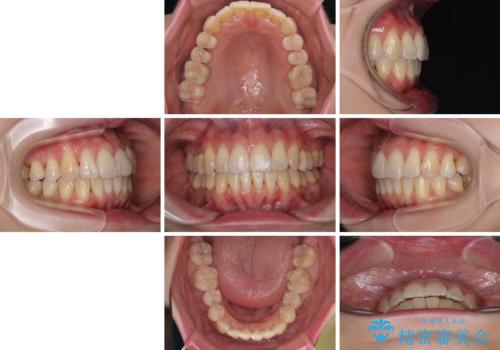

- 上下前歯のデコボコを気にして来院された患者様です。

デコボコは顕著であるものの、口元の突出感は強くないため、非抜歯にて矯正治療を行うこととしました。

装置はワイヤー装置でもマウスピースでも対応可能でしたが、より目立たない装置をご希望とのことで、インビザラインにて矯正治療を行うこととしました。

元々の叢生と歯肉退縮傾向になる歯肉であったため、ブラックトライアングルが目立つことが想定されました。

治療過程でブラックトライアングル改善のため、IPR(歯と歯の間を削る)を活用しました。